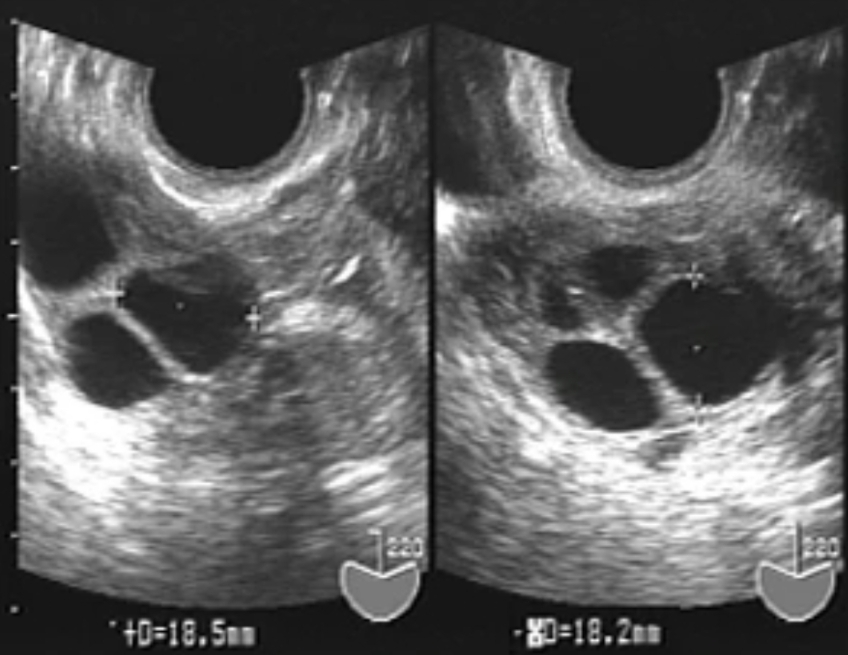

排卵後 卵胞 エコー 画像

排卵後 卵胞 エコー 画像のギャラリー

各画像をクリックすると、ダウンロードまたは拡大表示できます

超音波断層法検査とは耳では聞こえない高い周波数の音波を用いて、対象物を画像化する検査法です。 主に超音波を発信するプローベを腟内に挿入し、子宮内膜や卵胞 (卵子が入っている袋)の発育を観察する経腟超音波断層法を使用します。 排卵日を予測採卵前のエコーの個数と実際の採卵数が違うのはなぜですか? 掲載日:19年9月27日 卵子は卵巣の中の「卵胞」を満たしている「卵胞液」のなかにありますが、大きさは約01~02mmと小さいのでエコー画像で卵子を直接確認することはできません。 その